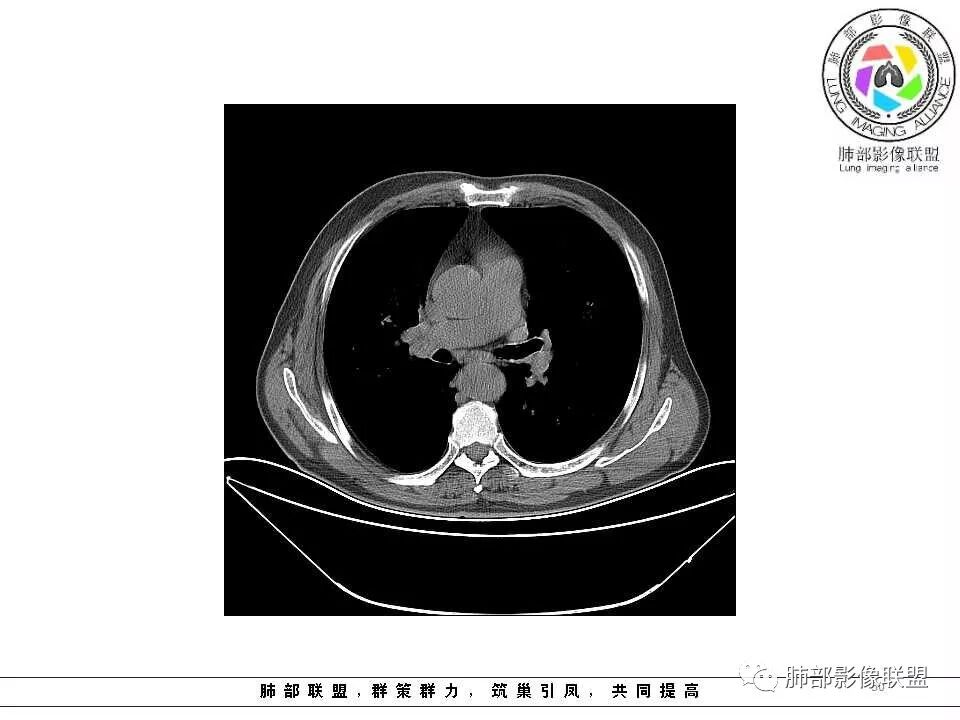

老年男性,两肺可见小叶中央型肺气肿,提示应该有抽烟史。2016年片,右肺门支气管稍模糊,考虑慢性感染,纵膈淋巴结稍大。但2017年左肺上叶新发占位,堵塞支气管,引起局部肺不张伴感染,且纵膈淋巴结较2016年变大,患者同时伴有咯血,考虑恶性。鳞癌?类癌?小细胞?

左肺上叶舌段支气管管壁略增厚 间隔一年 管壁增厚明显 向腔外突出形成结节 管腔闭塞 远端片状及斑片影 纵隔淋巴结增大 肺气肿背景 考虑鳞癌伴阻塞性炎症可能

老年男性,咯血1月,肺气肿背景,16年左肺上叶舌段结节,左肺门疑似淋巴结肿大,呈结节感。17年左肺上叶舌段见沿支气管走行分布结节 远端阻塞性肺炎,左肺门淋巴结肿大明显,首先考虑恶性病变,鳞癌?类癌?

老年男性,肺气肿背景,左肺上叶舌段一年前小结节后长大,实性,与邻近气管关系密切,远端有少许小片状炎症类小结节状,左肺门淋巴结肿大,首先考虑恶性,鳞癌可能性大,代排小细胞癌。病灶下方斑片状影,考虑炎症。

老年男性,肺气肿背景,对比前片,左肺上叶舌段结节较前进展,周围有斑片状条状密度增高影,左肺门淋巴结肿大,有咯血史抗炎后效果不佳,目测增强强化不好判断,考虑肺癌并阻塞性肺炎可能,鉴别炎症性肺癌,真菌类肺炎,肺脓肿,肺结核,建议完善肿瘤标志物,结核相关检查,病原体检查。

老年男性,咯血1月,肺气肿背景,左肺上叶舌段见沿支气管走行分布结节,呈葫芦样改变,左肺门淋巴结肿大明显,首先考虑恶性病变,小细胞癌可能